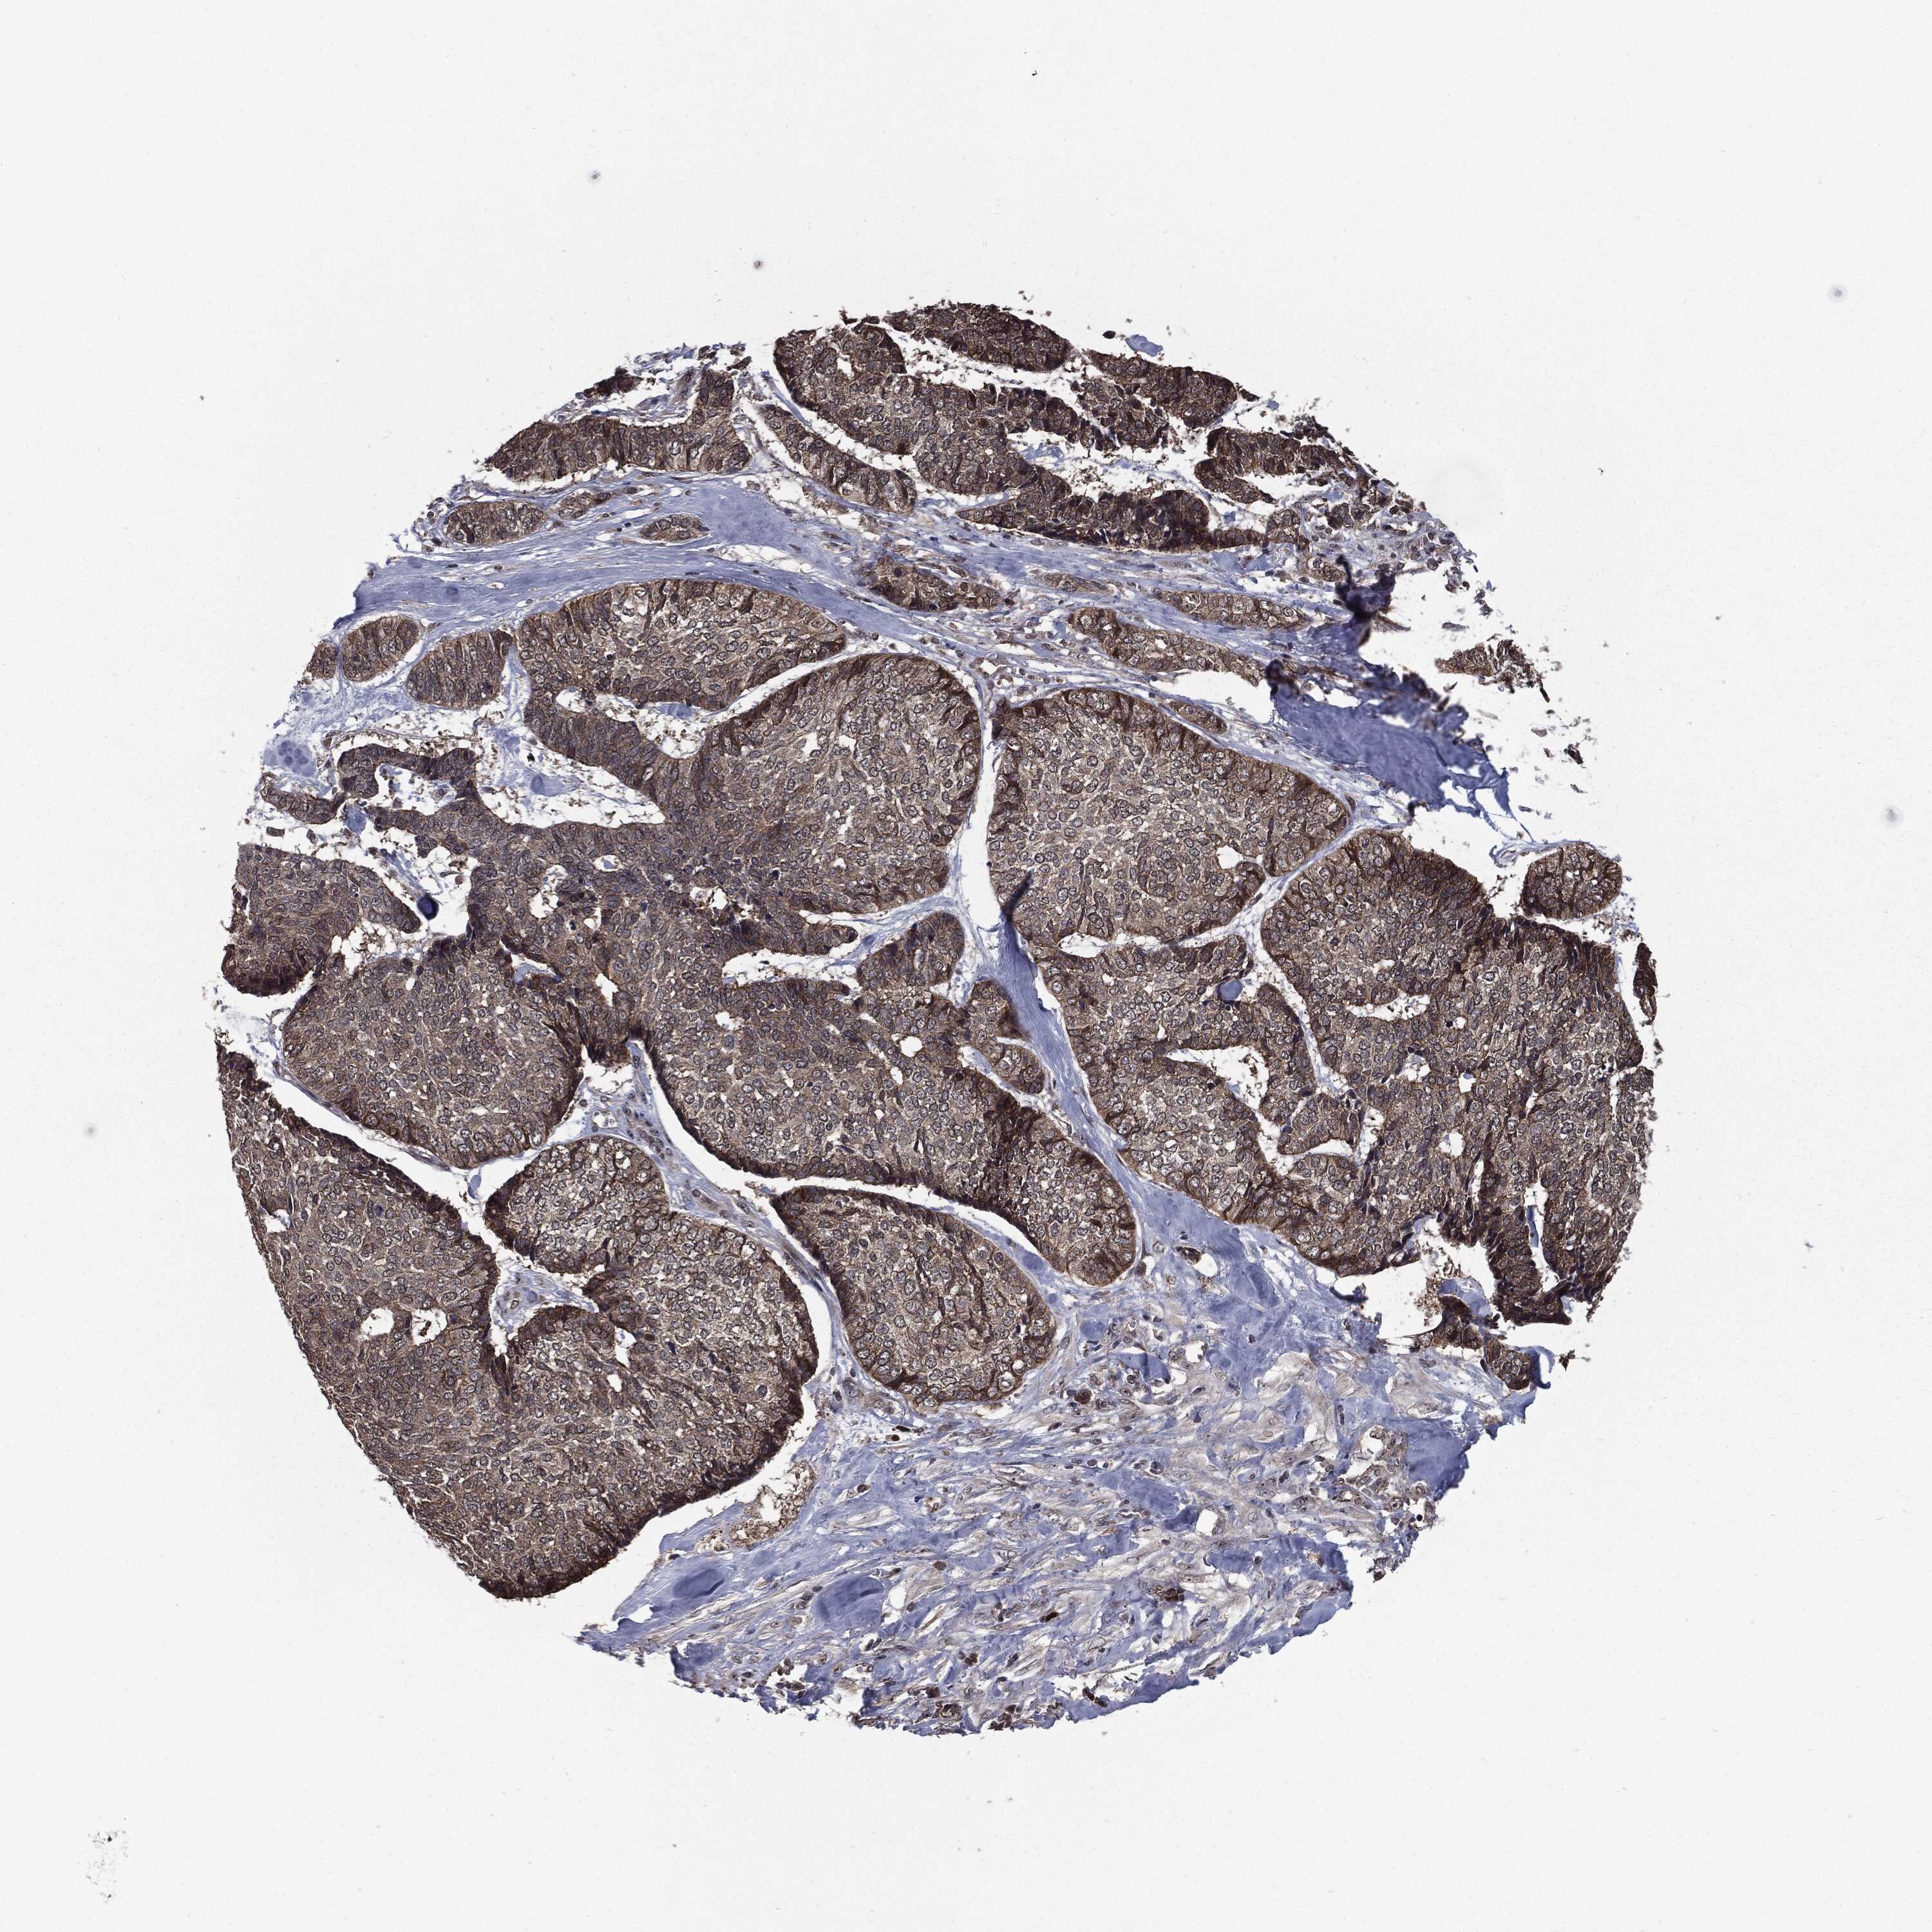

CANCER SKIN CANCER Show tissue menu

Basal cell and squamous cell cancer

SKIN CANCER - Protein expressioni

A mouse-over function shows sample information and annotation data. Click on an image to view it in a full screen mode. Samples can be filtered based on level of antibody staining by selecting one or several of the following categories: high, medium, low and not detected. The assay and annotation is described here.

Antibody stainingi

Antibody staining in the annotated cell types in the current human tissue is reported as not detected, low, medium, or high, based on conventional immunohistochemistry profiling in selected tissues. This score is based on the combination of the staining intensity and fraction of stained cells.

Each image is clickable and will lead to virtual microscopy that enables deeper exploration of all samples and also displays staining intensity scores, fraction scores and subcellular localization as well as patient and tissue information for each sample.

Squamous cell carcinoma, NOS

Squamous cell carcinoma, metastatic, NOS

Basal cell carcinoma

Papilloma, NOS